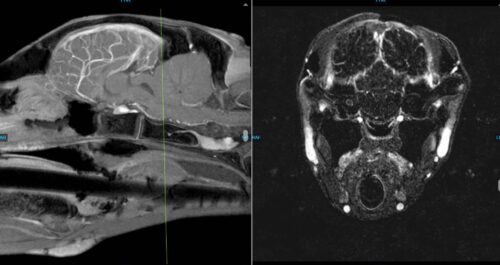

The following images are collected from the MRI of the brain of the foal. MRI collects images from multiple sequences to highlight different areas of normal brain tissue as well as potential pathology. The image on the left is taken as a cross section dividing the two hemispheres of the brain, and the image on the right is taken as a section shown through the green line on the image on the left. As you can see in the image on the right with the red arrow, there is an area of increased contrast within the cochlea of the right ear. This likely explains the foal’s clinical signs and the remaining brain appeared unremarkable.